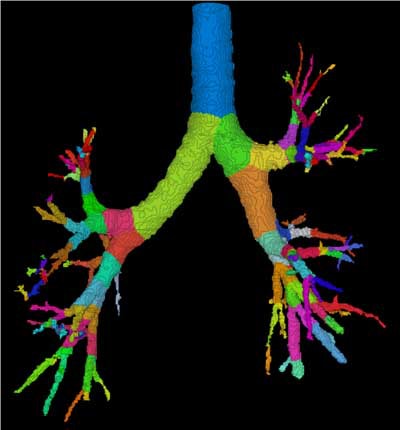

| Three-dimensional human airway tree acquired with CT at total lung capacity. First, an automated segmentation function located the centerlines, then based on the branching points of those centerlines, identified and color-coded individual airway segments. Quantitation is reported segment by segment. All images courtesy of Eric Hoffman, Ph.D. |

"The next step ... is being able to identify not only the lungs but the lobes, airways and blood vessels," he said. This process begins with finding the centerline of the airway tree, and then using the branch points as a road map. "We can then link those (branch) points from one volume to the next lung volume so you can accurately track an individual voxel within the lung across multiple lung volumes," he said. "A simple density change measurement in the parenchyma gives you an index of regional ventilation. It also gives us a way to then map an individual across time if there's a slight ... change in body configuration and so forth."

Branching patterns in the first 7 or 8 generations of the airway tree show great commonality among individuals, he said, but the branches become highly differentiated as they get smaller --so much so that an individual's branching pattern is considered a better marker of individuality than fingerprints, he said.